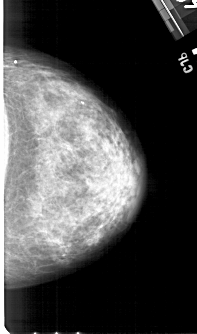

A_1427_1.LEFT_CC

LEFT_CC LINES 4861 PIXELS_PER_LINE 2791 BITS_PER_PIXEL 12 RESOLUTION 43.5 OVERLAY